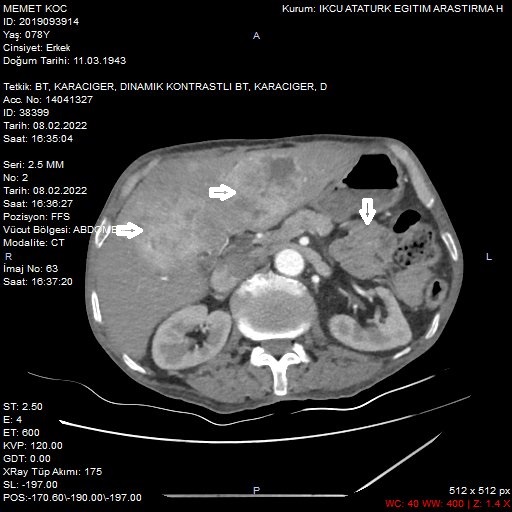

A 77-year-old male patient was referred to the surgical outpatient clinic with complaints of increasing fatigue, weakness, and abdominal pain for the last three months. On ultrasound and abdominal computerized tomography (CT), malignant masses were detected in the liver and spleen. No pathological data were found in the laboratory tests of our patient, whose tumor markers were normal. Heterogeneous hypodense lesions were detected in the liver segment 5 to 8 and in the upper pole of the spleen by whole-body positron emission tomography (PET)-CT performed on the patient. It has been reported that lesions with pathologically increased F18-FDG uptake have malignant characteristics. The patient underwent central hepatectomy and splenectomy (Figure 1).

Figure 1

Figure 1. This figure shows synchronous lesions in the liver and spleen on abdominal CT (A) and PET/CT (B).